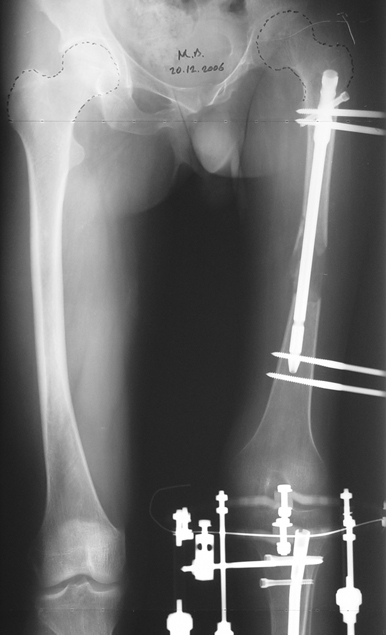

3. POSTTRAUMATIC LOWER LIMB SHORTNESS (MALUNION)

This type of shortness occurs after a fracture heals in a shortened position. Most cases are seen in adults and can be treated with one lengthening operation. Additional deformities can be corrected simultaneously. Most of these cases can be treated with lengthening over nail or just corrections and intramedullary nailing.